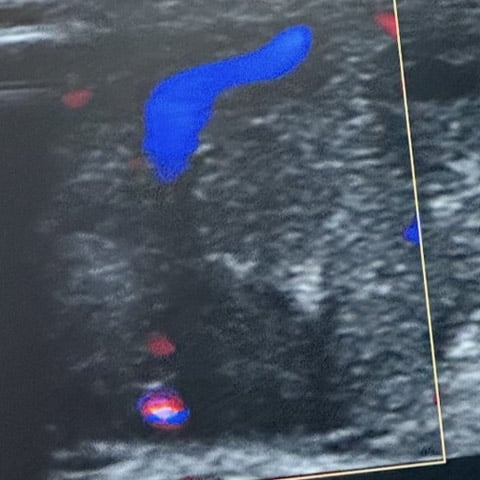

MR-angiography

AV malformation with multiple feeding arteries and irregular capillary blush with non-uniform distribution.

Normal arteries are embedded in the tumor blush.